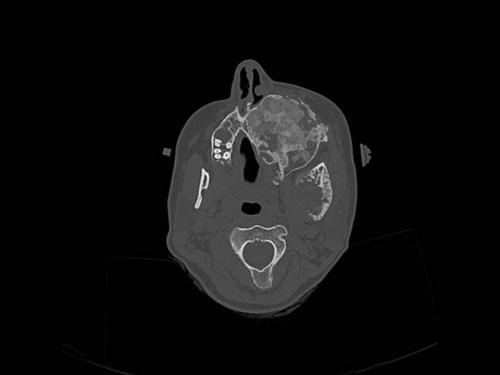

Knochendeformitäten seit der Geburt

Fall-ID: 712

ICD: M85.09

Autor*in: Sandra Klipp

Eine 16-jährige Patientin kommt in eine MKG-chirurgische Praxis zur Abklärung der weiteren Vorgehensweise bzgl. ihrer Erkrankung.

Sie betrachten die angefertigten Röntgenbilder. Welche der folgenden Röntgenbefunde ist korrekt? Ossäre Auftreibungen im Bereich …

- A… der Mandibula links.

- B… des Os frontale links.

- C… des Os zygomaticum links.

- D… des Os temporale links.

- EAlle genannten Aussagen sind korrekt.

Bildgebung - OPAN 2004